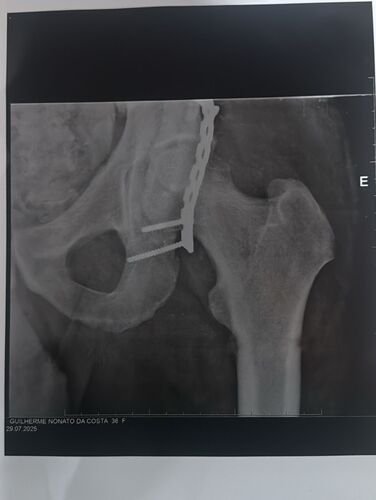

No acidente, Guilherme teve uma fratura gravíssima no acetábulo — uma lesão rara e de alto risco. Ele precisou ser encaminhado com urgência para Governador Valadares, onde passou por duas cirurgias complexas. Apesar de toda a luta e cuidado, o resultado dessas intervenções o deixou impossibilitado de andar.

Com muita força e determinação, Guilherme iniciou sessões de fisioterapia, buscando recuperar seus movimentos. No entanto, uma complicação cirúrgica inesperada interrompeu esse processo e trouxe uma nova e difícil realidade: sem uma prótese específica, ele não conseguirá voltar a andar.